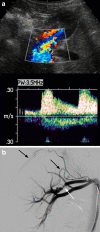

Renovascular disease (RVD) is an important cause of hypertension in children, as it often is amenable to potentially curative treatment. Imaging aimed at finding RVD therefore needs to have high sensitivity so as not to miss important findings. Digital subtraction angiography is the gold standard investigation. Doppler ultrasonography, computed tomography (CT) angiography and magnetic resonance (MR) angiography can all be helpful, but none has, at present, high enough sensitivity to rule out RVD in a child with a suggestion of that diagnosis.